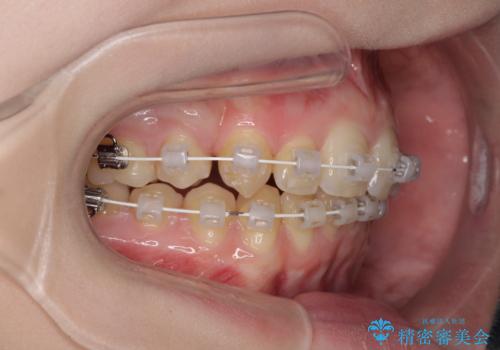

八重歯を短期間で改善 ワイヤー装置による抜歯矯正

- 矯正装置

- 審美装置

- 治療期間

- 1年6ヶ月

- 著しい八重歯を気にして来院された患者様です。

片側の八重歯であり上顎の正中がずれていたため、上顎左右第一小臼歯2本を抜歯して排列することとしました。

下顎の骨格的なズレが大きかったため、上下歯列のバランスが取れるか心配でしたが、上下ともに左右対称に近い歯列で治療を終えることができました。